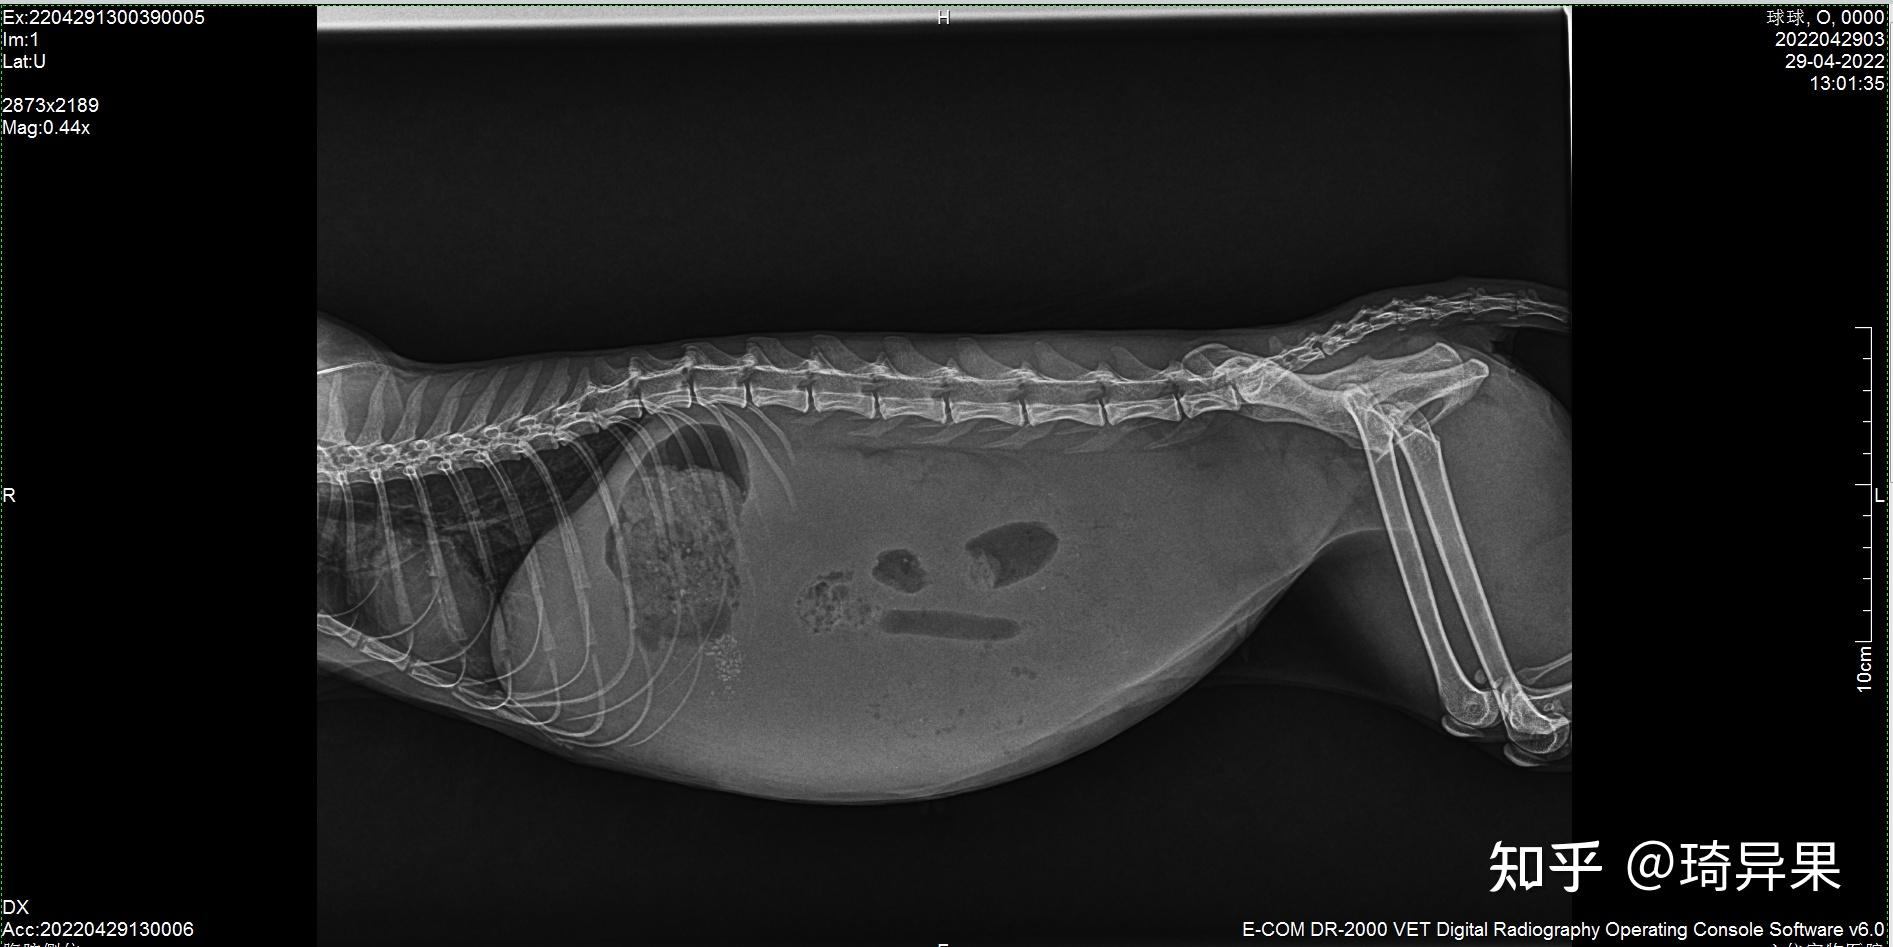

猫传腹最详细治疗记录,帮你治疗传腹少走弯路 - 知乎

猫腹水了我没钱去做生化拍了片子逆推了传腹在筹钱治疗